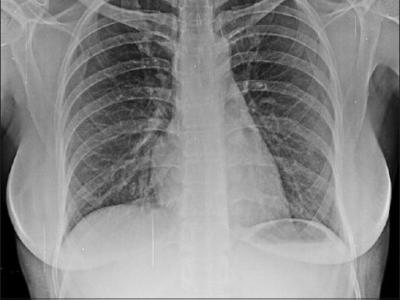

Psoriatic Arthritis at Risk for Interstitial Lung Disease A TriNetX EHR study shows that psoriatic arthritis (PsA), but

Psoriatic Arthritis at Risk for Interstitial Lung Disease A TriNetX EHR study shows that psoriatic arthritis (PsA), but not Psoriasis (PsO), patients are at increased risk for interstitial lung disease (ILD). https://t.co/2zuxF1PY3Q. https://t.co/r28dY3T8nO